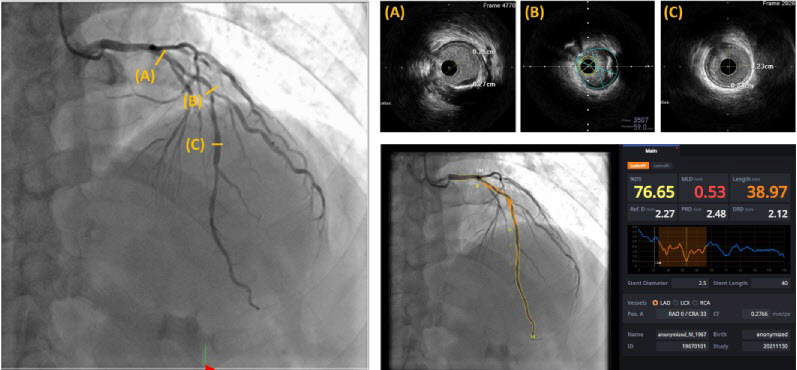

스텐트 삽입술 전에 심혈관 모양과 협착 여부를 파악할 수 있는 심혈관 조영술을 시행하는데 심혈관 조영술은 영상이 복잡하고 작은 혈관 안의 3차원 구조를 모두 파악하기 어려운 단점이 있다.

때문에 스텐트 시술이 필요한 환자의 4명 중 1명은 심혈관의 정확한 평가를 위해 고가의 의료장비(약 180만원)인 혈관 내 초음파를 추가로 사용하고 있는 실정이다.

이에 교수팀은 심혈관을 자동으로 분석해주는 인공지능 소프트웨어(AI-QCA)가 혈관 내 초음파를 대체할 수 있는지 알아보기 위해 혈관 내 초음파를 추가로 시행한 환자 47명을 대상으로 ▲협착된 직경 백분율 ▲ 협착된 영역 백분율 ▲병변 길이 ▲ 최소 내강면적 등의 결과가 인공지능 소프트웨어 결과와 얼마나 일치하는지 확인했다.

그 결과 시술시 중요한 지표인 혈관의 직경 및 넓이, 병변의 길이가 혈관 내 초음파 검사로 측정한 지표와 인공지능 소프트웨어로 측정한 지표가 최소 60%에서 최대 80%까지 상관성을 보이는 것으로 나타났다. 또한 병변 식별률은 88.7%, 병변 크기의 차이는 10mm 내외로 큰 차이가 없었다.

특히 AI 소프트웨어는 실시간으로 심혈관의 병변 여부, 병변의 길이, 직경 등의 정보를 제공하여 스텐트의 길이와 직경을 결정하는데 도움을 줄 수 있다. 이에 따라 의사의 높은 숙련도를 요구하는 스텐트 시술에 인공지능 소프트웨어를 병행해서 사용한다면 더욱 효과적인 검사 및 시술을 할 수 있을 것으로 보인다.

강시혁 교수는 "본 연구를 통해 숙련된 심혈관 시술자가 고가의 의료장비의 혈관 내 초음파로 분석한 결과와 인공지능 소프트웨어의 분석 결과가 최대 80%까지 상관성이 있음을 알 수 있었다"며 "복잡한 스텐트 시술에 인공지능을 활용한다면 경제적인 부담을 줄이면서도 시술의 정확도를 높일 수 있을 것으로 기대한다"고 밝혔다.

문인태 교수는 "심혈관 스텐트 시술은 적절한 크기의 스텐트를 합병증 없이 안전하게 넣은 것이 핵심"이라며 "이 연구만으로 인공지능의 능력을 평가할 수는 없지만 인공지능으로 분석한 수치 값이 시술 중 참조할 수 있는 지표로 활용될 수 있음을 확인한 것에 의의가 있다"고 말했다.